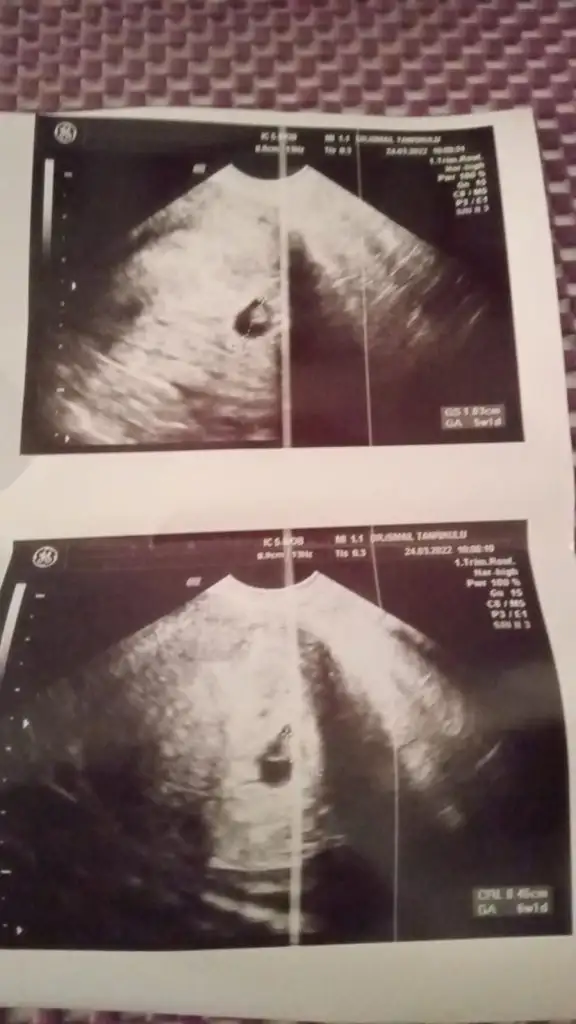

kuzum başka görüntün var mı? bence kız gibi ama yine de ayrıntıyla bi bakayım10+4 karından ultrason

kuzum bu tosunpaşaya benziyorCanım ben de bir cinsiyet tahmini alabilir miyim ? Karından bakıldı ve 6 haftalık suan. Eki Görüntüle 3033530

kuzum bu prenses gibi